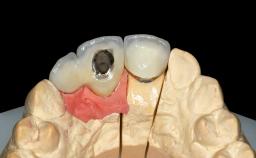

A 30-year-old woman was referred by her general dentist for evaluation of an esthetic complication related to previous implant treatment for congenitally missing maxillary lateral incisors. The patient’s chief complaint was the inadequate esthetic appearance of her smile. The case demonstrates the use of a combined approach to achieve optimal results. Two different flap designs - a tunnel technique and a coronally advanced flap - are employed based on the surgical objectives for the affected site.

Type of Implants Two-Piece

Attachment Two-Piece

Abutment Type Standard

Prosthesis Type FDP